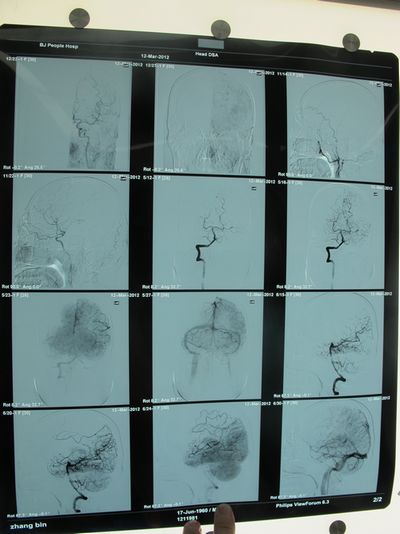

患者张某某,男性,52岁,主因“言语不利,右侧肢体无力3个月”入院。患者近3个月前无明显诱因出现间断额部搏动性头痛,4日前晨起后出现口角左偏,言语不利,理解困难,右侧肢体无力,无肢体麻木,无饮水呛咳及吞咽困难,伴反应迟钝,行为异常,于人民医院住院治疗。入院后行全脑血管造影示:左侧颈内动脉起始部重度狭窄,予抗血小板聚集、改善循环、调脂稳定斑块等治疗后,患者病情稳定出院。出院后患者继续坚持口服用药,于外院康复治疗,患者言语不利及右侧肢体无力较前好转,后未进一步诊治再次收入院。

2012年5月17日,张勤奕教授为其施行了左侧颈动脉内膜剥脱术,手术圆满成功,患者术后恢复良好。